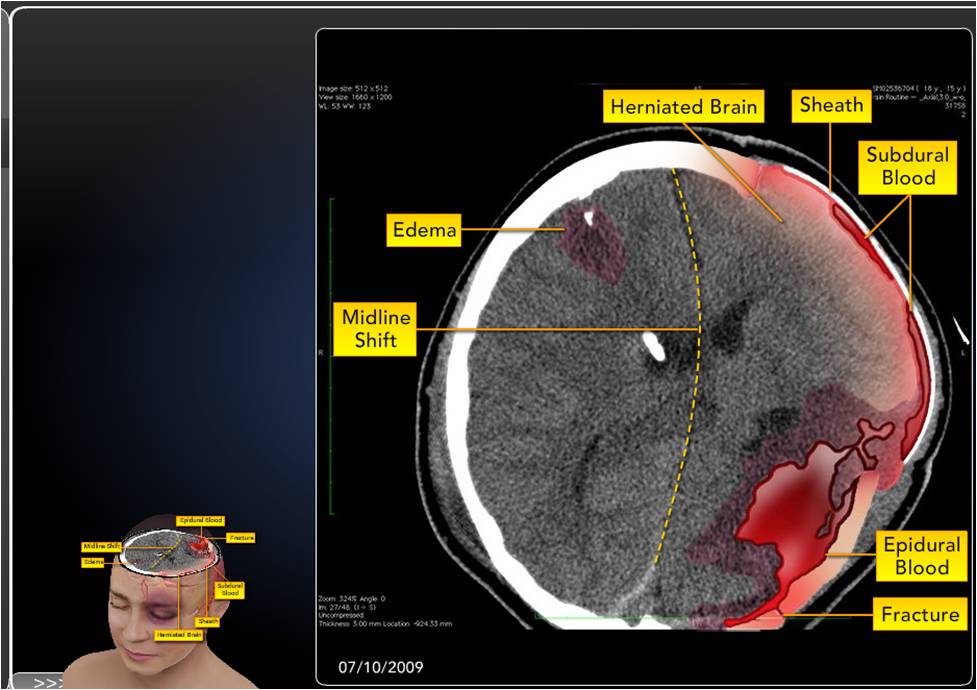

She has 2 brain surgeries in 24 hours.

Julia has a broken skull, broken lumbar spine, and her brain is so swollen they have to remove half of her skull to relieve the pressure. Half of her brain is literally outside of her skull for 4 months until the swelling subsides.

It is that horrible swelling that causes the damage to the left side and front of her brain.

She has 2 brain surgeries in 24 hours.

Julia has a broken skull, broken lumbar spine, and her brain is so swollen they have to remove half of her skull to relieve the pressure. Half of her brain is literally outside of her skull for 4 months until the swelling subsides.

It is that horrible swelling that causes the damage to the left side and front of her brain.